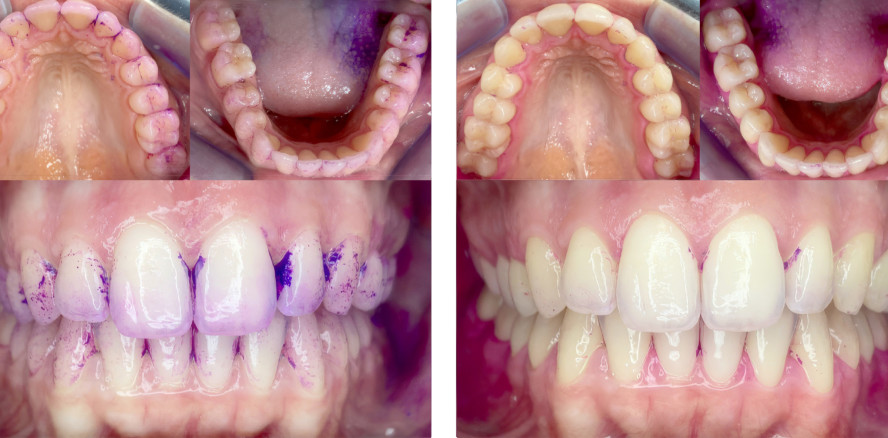

Die Vergleichsstudie war in drei Untersuchungen unterteilt. Der Untersuchung zur Baseline folgten zwei Follow-ups: das erste nach einer Woche und das zweite nach einer weiteren Woche. Alle zehn Proband/-innen, die geläufig mit einer oszillierend-rotierenden Zahnbürste putzten, kamen nach informiertem Einverständnis zur Untersuchung zur Baseline mit seit 24 Stunden ungeputzten Zähnen. Vor Beginn der klinischen Untersuchungen erfolgte eine erneute Instruktion für die Anwendung der oszillierend-rotierenden Zahnbürste. Klinisch untersucht wurden die Rezessionen (REZ), die Sondierungstiefen (ST), das Clinical Attachment Loss (CAL), der Papillen-Blutungs-Index (PBI), das Sondierungsbluten „Bleeding on Probing“ (BOP) und der modifizierte visuelle Gingivaindex (MGI). Im Anschluss an die Aufnahme dieser gingivalen und parodontalen Parameter wurden die Zähne mit einer Plaquerevelator-Lösung angefärbt und die Plaqueablagerungen mittels Quigley-Hein-Index (QHI) dokumentiert. Außerdem erfolgte eine fotografische Dokumentation des angefärbten Biofilms. Im Anschluss putzten die Proband/-innen die Zähne mit der „Oral-B® iO“. Nach dem Zähneputzen wurden die Zähne erneut angefärbt und der QHI wiederholt im klinischen Referenzformblatt (KRF) dokumentiert und die Situation fotografisch festgehalten (Abb. 4 und 7). Alle Proband/-innen bekamen im Zuge der Studie zur Baseline die neu zur Verfügung gestellte Schallzahnbürste von zahnco®. Außerdem erhielten sie eine Instruktion nach der Tell-Show-Do-Methodik für die Anwendung der Schallzahnbürste. Die Proband/-innen sollten sich zweimal täglich für mindestens zwei Minuten über einen Zeitraum von zwei Wochen die Zähne mit der Schallzahnbürste putzen. Dabei verwendeten alle Proband/-innen fluoridhaltige Zahnpasta. Wenn die Proband/-innen üblicherweise eine Interdentalraumpflege durchgeführt haben, sollten sie das auch weiterhin tun.

Nach einer Woche erfolgte das erste Follow-up. Die Proband/-innen kamen erneut, ohne für 24 Stunden im Vorfeld ein häusliches mechanisches Biofilmmanagement durchgeführt zu haben. Alle klinischen Untersuchungen aus der Untersuchung zur Baseline wurden wiederholt. Nach Anfärben erfolgte das Putzen der Zähne diesmal mit der Schallzahnbürste, gefolgt von einer erneuten Anfärbung der Restbeläge mit fotografischer Dokumentation (Abb. 5 und 8).

Eine Woche nach dem ersten Follow-up wurde das Follow-up 2 durchgeführt. Das Vorgehen von Follow-up 2 war das Gleiche wie bei dem Follow-up 1 (Abb. 6 und 9).